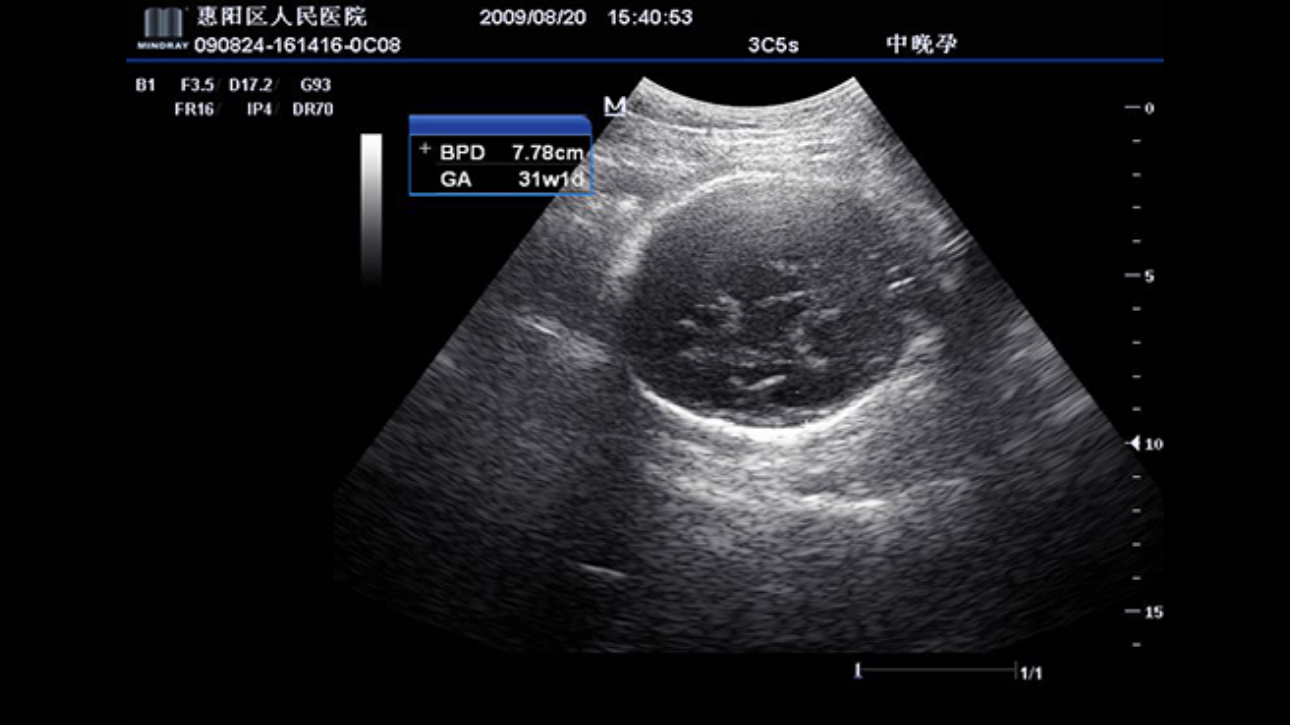

A fully-featured laptop style color Doppler system, M5 offers uncompromised 2D performance and exceptional value in a highly convenient and easy to use package. Equipped with advanced technologies such as Smart 3D TM and efficient workflow software, makes M5 ideal for use within obstetrics and gynecology application field.

Smart 3DTM

Freehand 3D fetal image rebuilding for more informative observation.